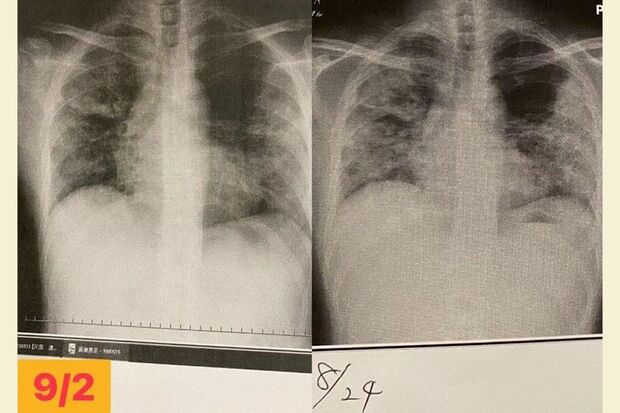

右・8月24日、東京1回目の入院で、退院2日前、左・9月2日、愛知県の病院で撮ったレントゲン写真(写真:取材者提供/東洋経済オンライン)

[写真 5/7枚目] 右・8月24日、東京1回目の入院で、退院2日前、左・9月2日、愛知県の病院で撮ったレントゲン写真(写真:取材者提供/東洋経済オンライン)